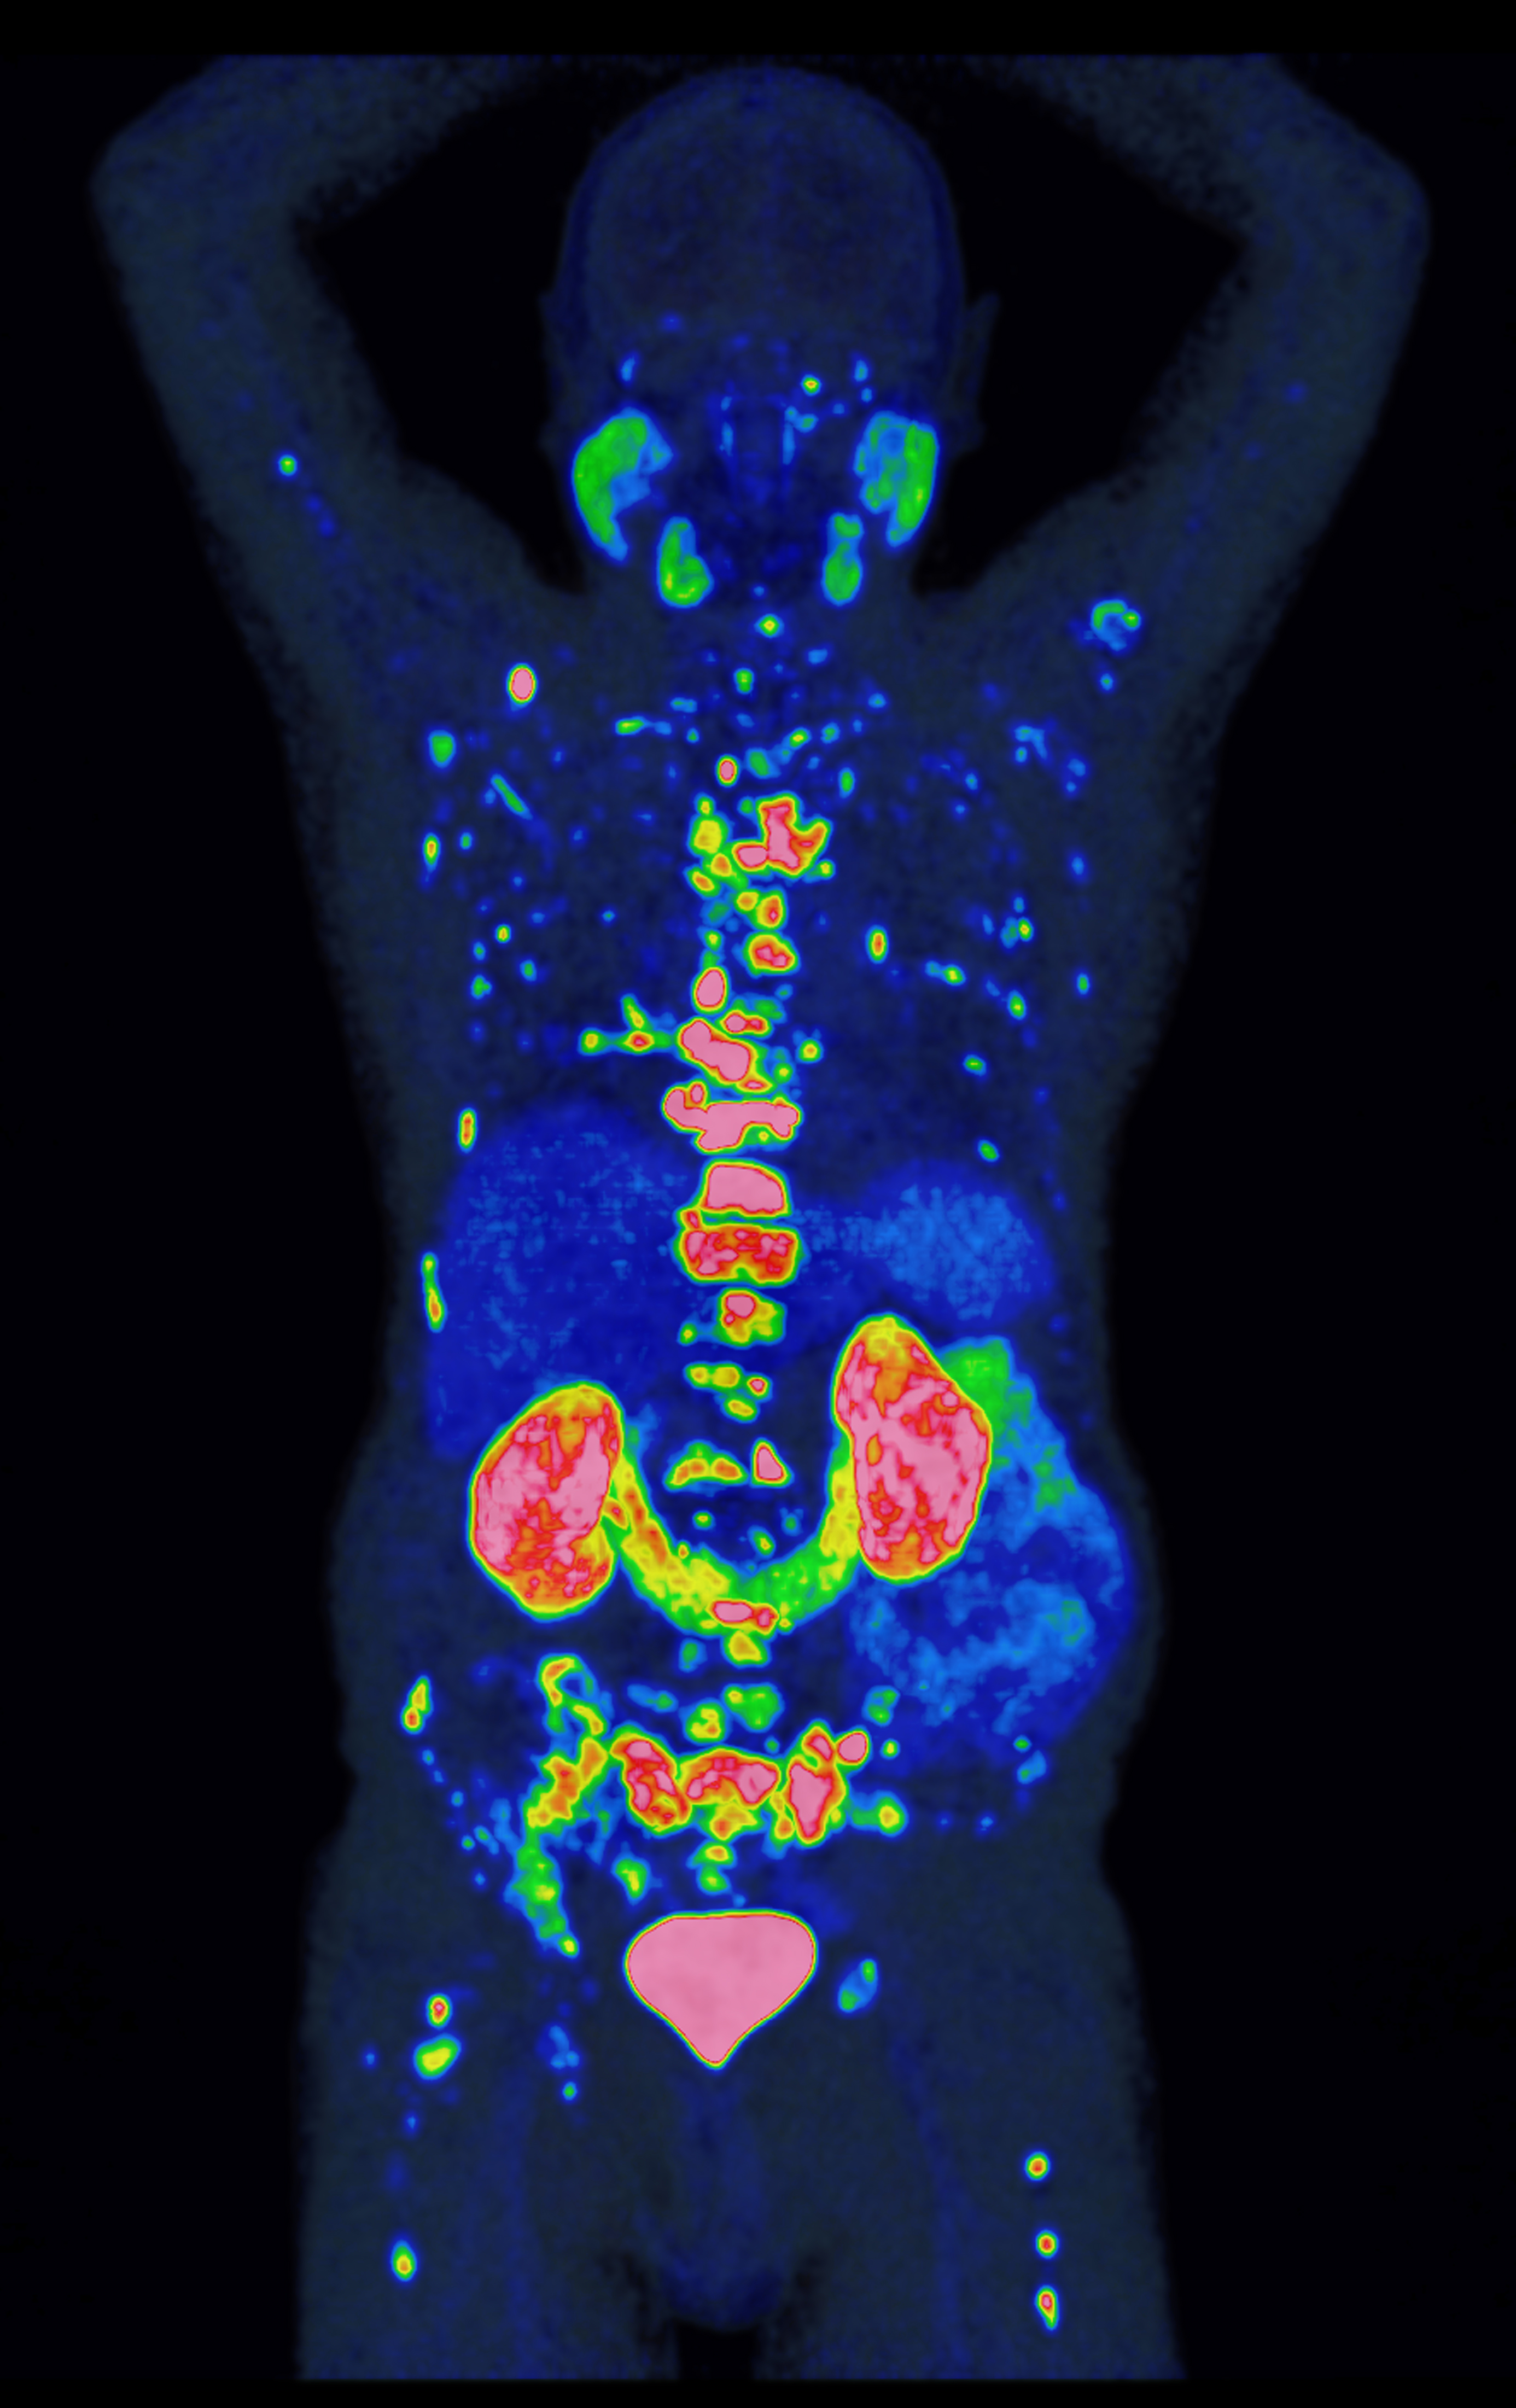

Das PROMISE-Team nutzte für die Risikobewertung die PSMA-PET**, ein hochmodernes Bildgebungsverfahren, mit dem sich Prostatakrebszellen besonders präzise und ihr Ausbreitungsstadium im Körper sichtbar machen lassen. Da die Methode empfindlicher ist als ältere Verfahren, mussten ihre Befunde zunächst in neue Behandlungsempfehlungen übersetzt werden – ein Prozess, den PROMISE maßgeblich geprägt hat. In einer der größten Studien weltweit wertete das Team Bilddaten von über 15.000 Patienten aus. Gemeinsam mit international führenden Forschungseinrichtungen entwickelte es daraus das PROMISE-Schema – eine Methode, mit der sich individuelle Risikoprofile auf Basis der PSMA-PET deutlich präziser bestimmen lassen. Darauf aufbauend entstanden Nomogramme, also Vorhersagemodelle für das individuelle Risiko, die für Ärzt:innen und Patient:innen verständlich aufbereitet und zur gemeinsamen Therapieentscheidung nutzbar sind.